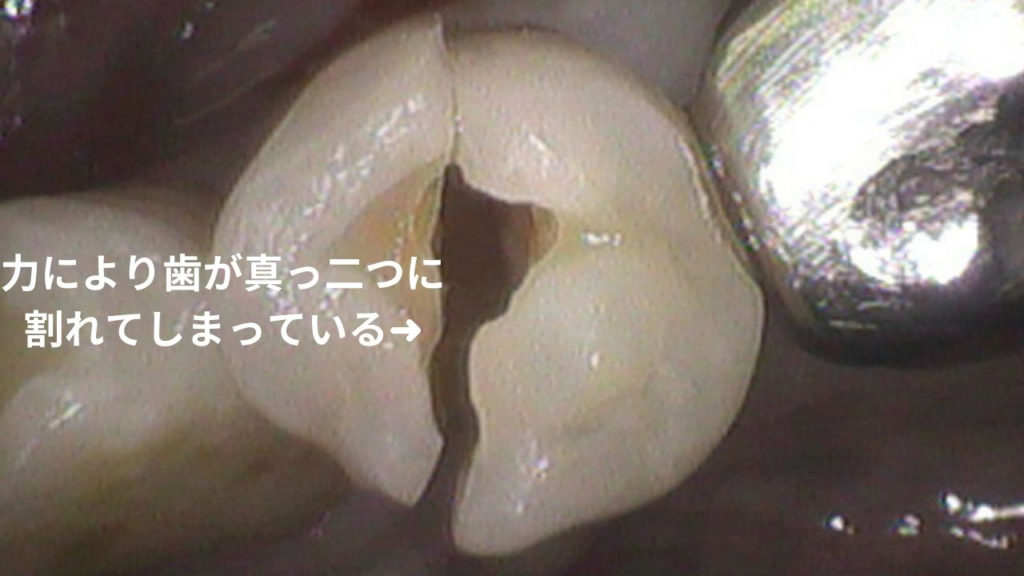

この写真をご覧ください。

これはいずれも歯が割れたり、歯の根が折れてしまった症例です。

このように歯が真っ二つに割れたり